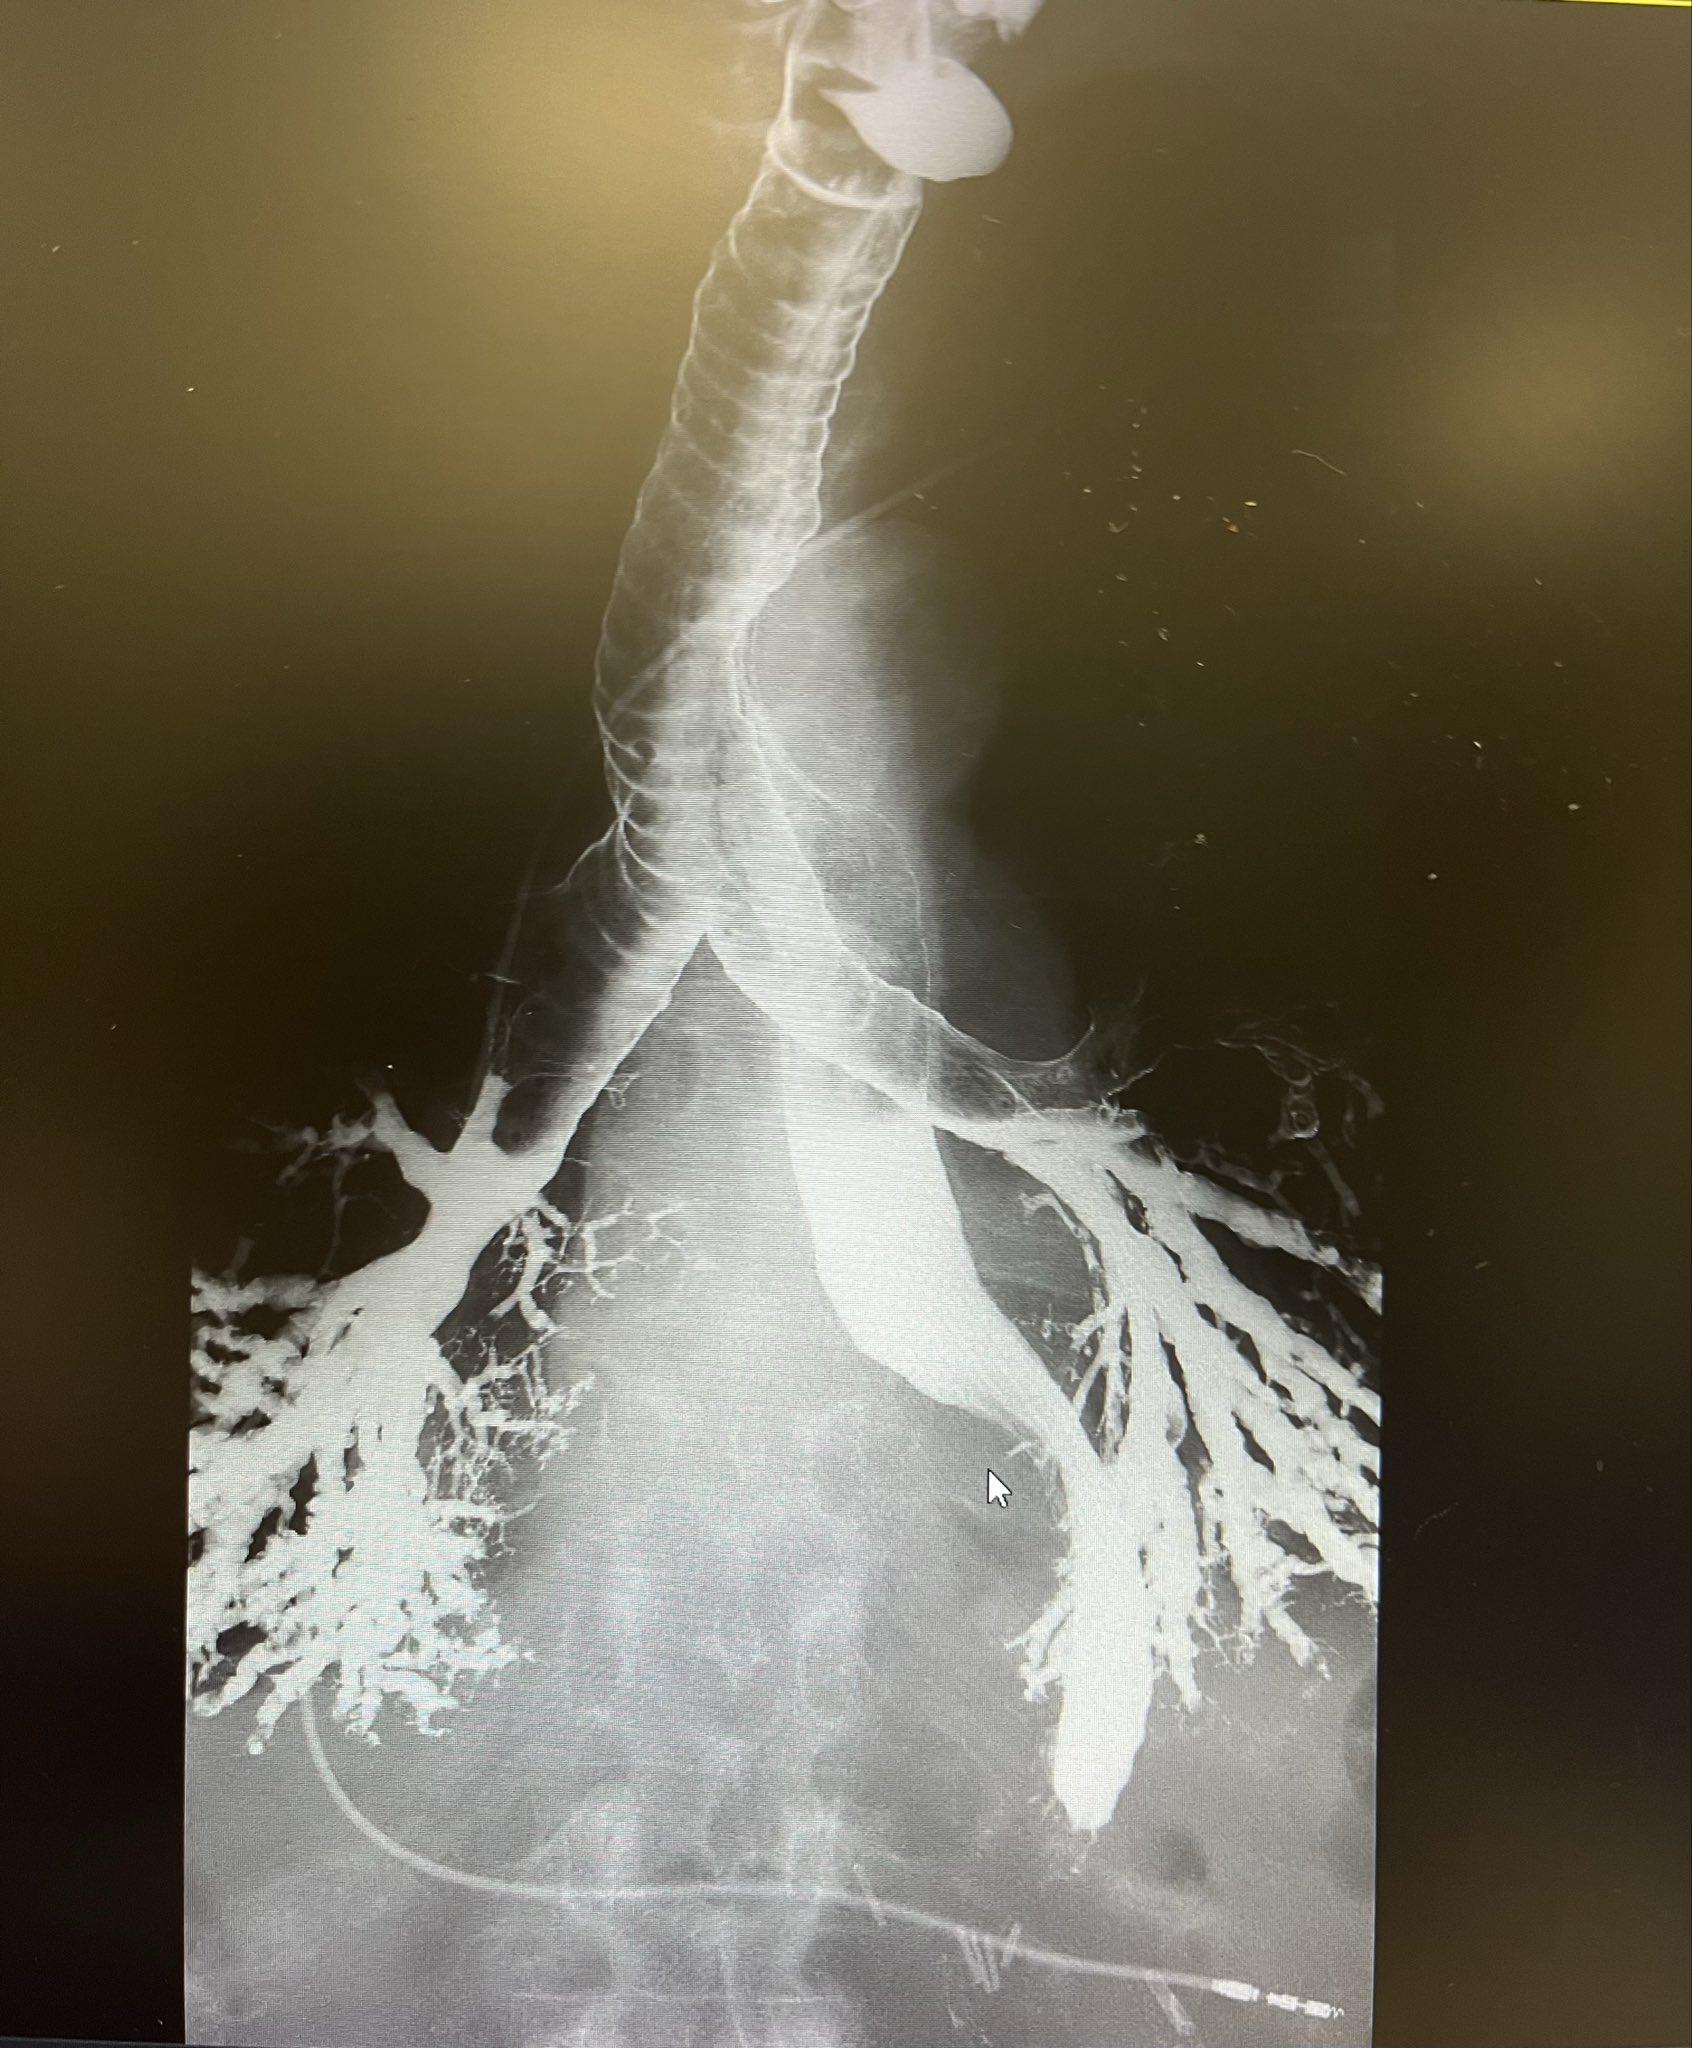

Hepatic vein thrombosis in a young or otherwise unexplained case should prompt a hypercoagulability workup.